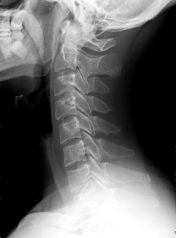

レントゲンやMRIではわからないのが事故の症状であり

患者様の訴えをどうこちら側が理解するかも大切なことです。